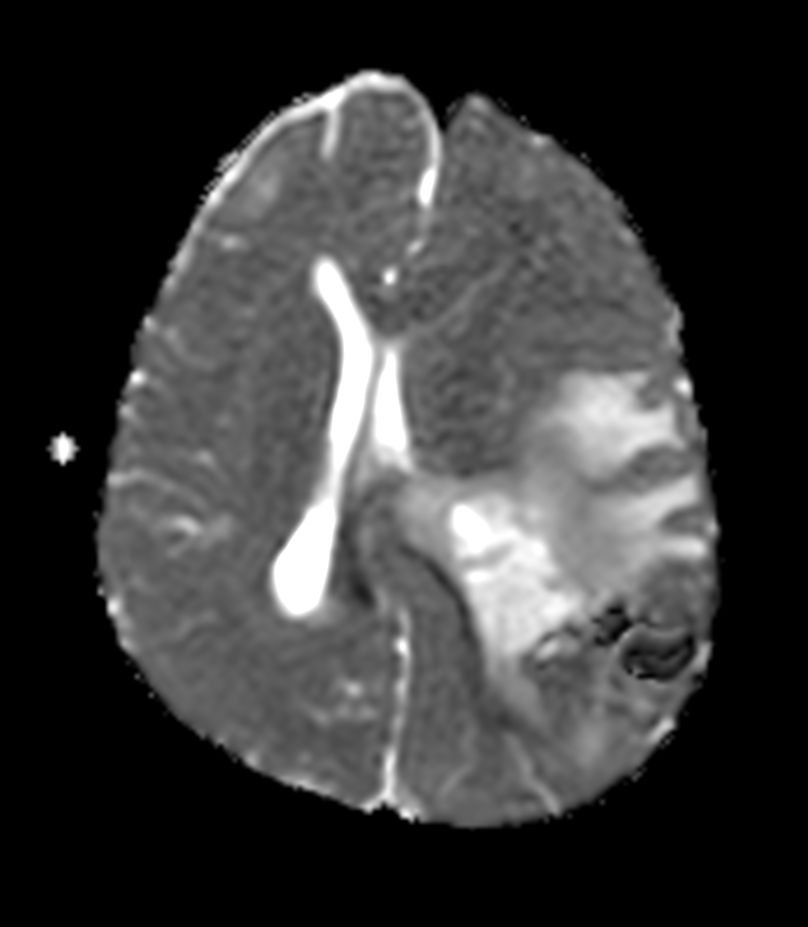

Pediatric Brain with hemorrhagic mass

Pediatric patient with a hemorrhagic mass in the brain